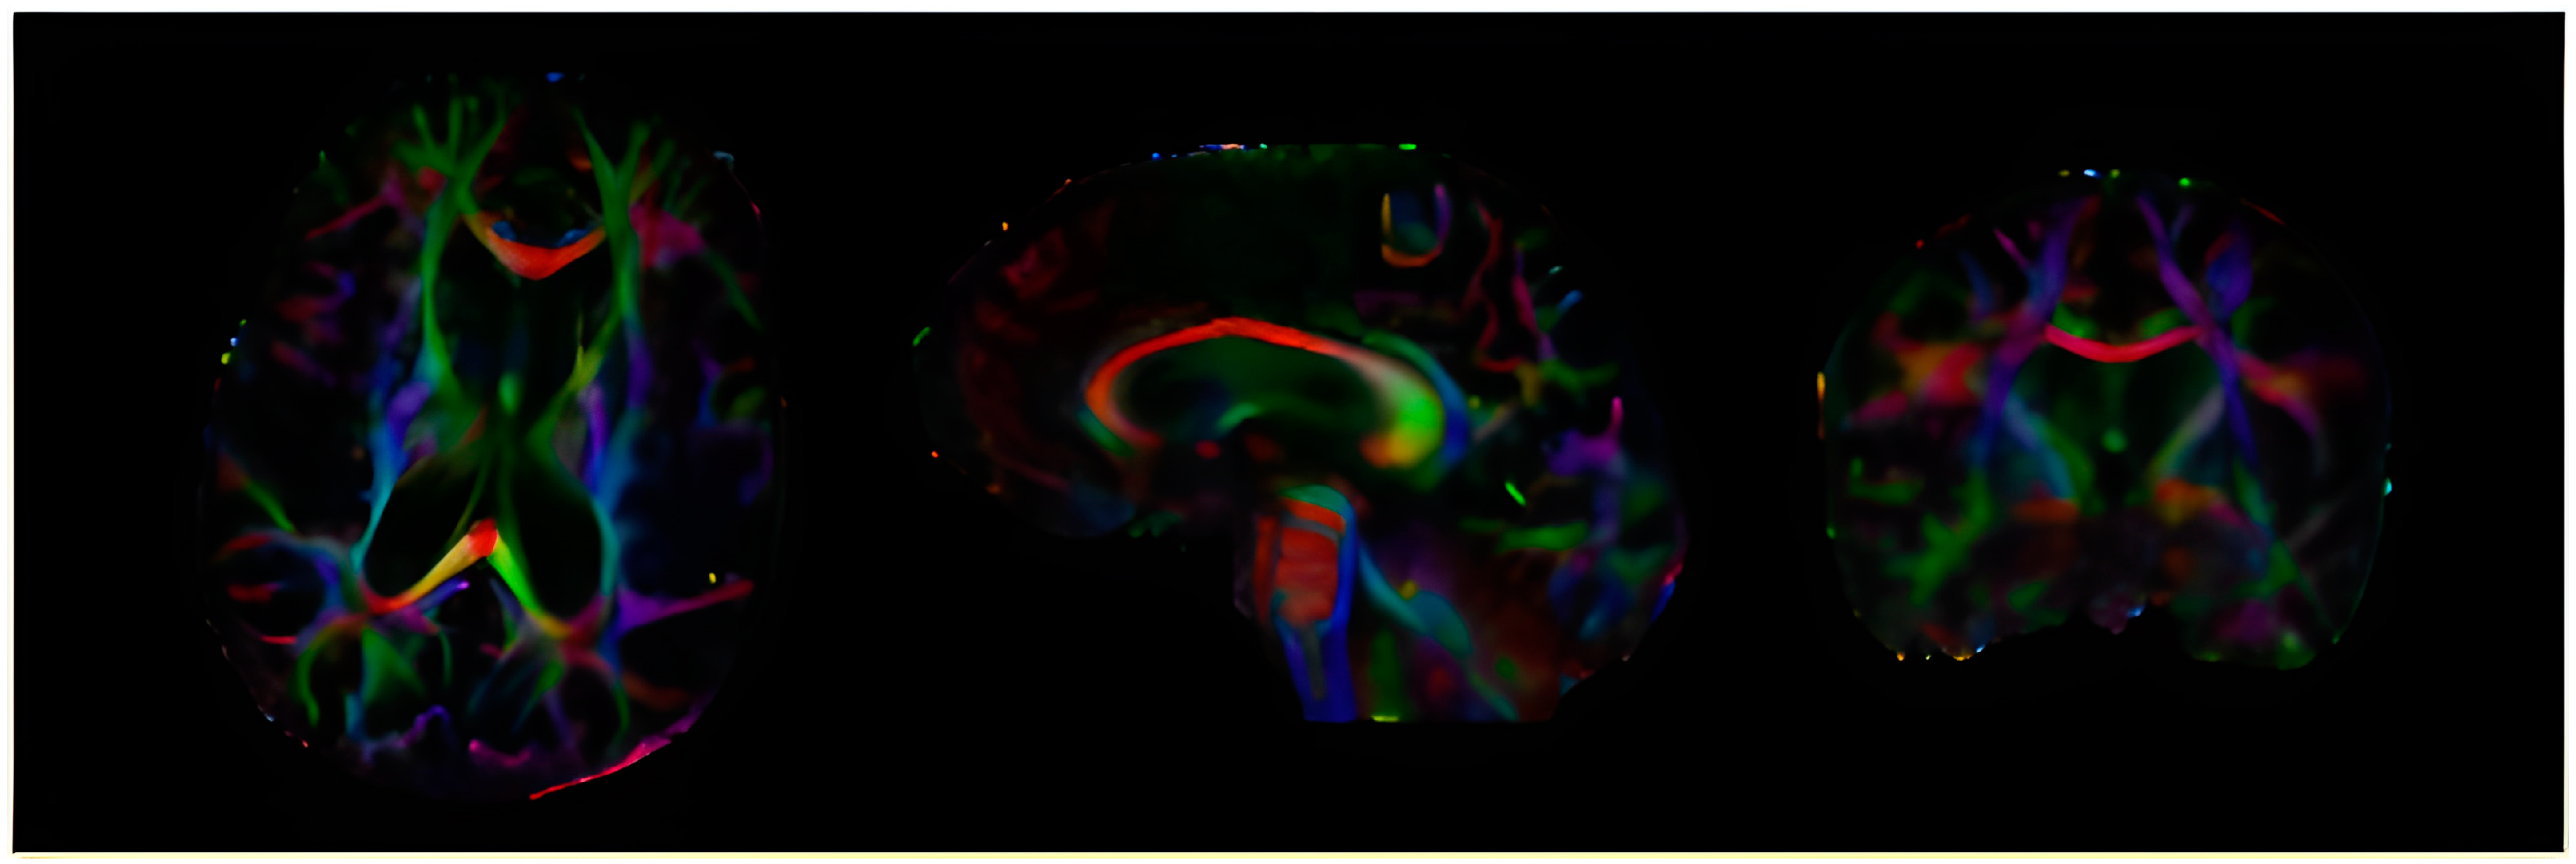

2.2. MRI Acquisition Protocol and Fractional Anisotropy Calculation

- DTI (technical parameters—32 directions, b = 0 and 1000 s/mm2, diffusion direction—tensor, FOV 23.2, layer thickness 2 mm, TE 100);